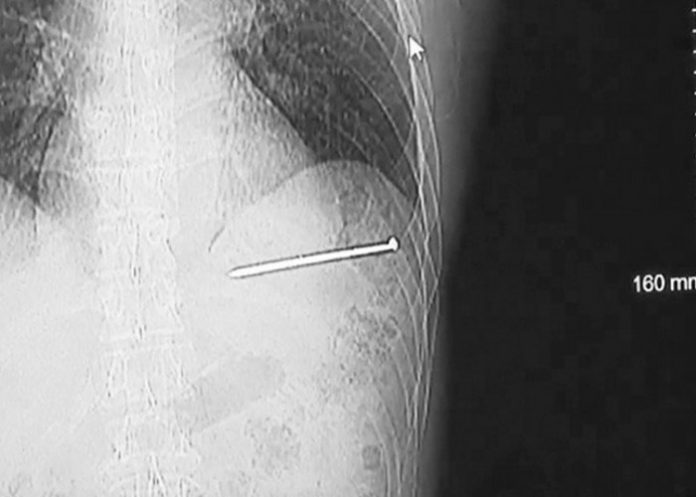

El estadounidense Doug Bergeson trabajaba en la chimenea de su vivienda de Wisconsin, en el norte del país, cuando sufrió un accidente que podría haberle costado la vida. Una pistola de clavos se disparó por accidente y le ocasionó una grave lesión cardíaca, publicó el sitio del canal WBAY TV.

Aunque primero pensó que los clavos solo le habían "rozado", al ver que uno incrustado en su pecho se movía con cada latido del corazón pensó: "Esto no es bueno". Entonces, se lavó la sangre y, como estaba solo en su casa, subió a su vehículo y manejó algo más de 19 kilómetros hasta el hospital.

"Estaba moviendo la pistola de clavos hacia adelante, de punta, había poco espacio y se disparó antes de que estuviera realmente lista. Luego cayó y volvió a disparar", recuerda Bergeson el momento en que un clavo le impactó en el pecho a la velocidad de una bala.

Ya en el hospital, mientras era examinado, avisó de lo sucedido a su esposa y, posteriormente, fue trasladado hasta otro centro médico para ser intervenido. La cirugía ha sido exitosa y Bergeson solo ha perdido una arteria, aunque los médicos advirtieron de que si el clavo le hubiese penetrado en otra posición podría haber acabado con su vida.